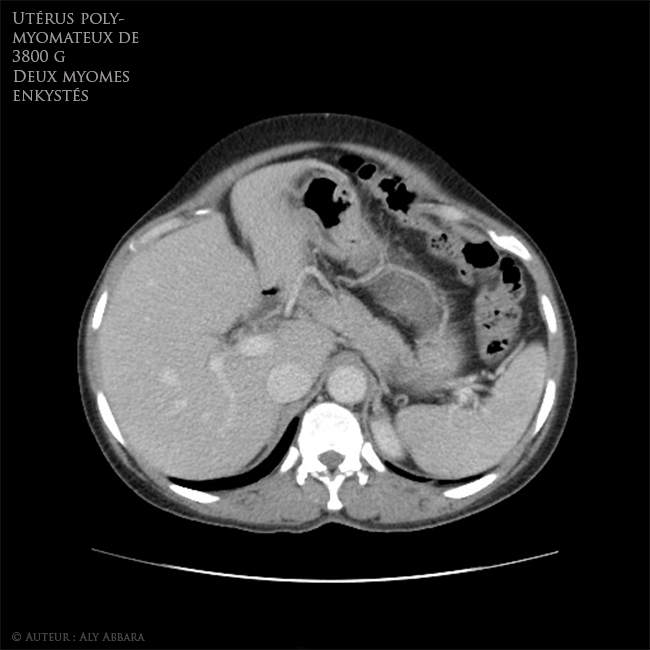

Utérus polymyomateux de 3800 g comportant deux volumineux myomes enkystés - Imagerie par scanner - coupes axiales

Images Scanner (coupes axiales) montrant un volumineux utérus polymyomateux pesant environ 3800 grammes et comportant deux myomes enkystés (kystes sous séreux utérins par dégénérescence kystique de fibromes) de 95 cm3 et 1661 cm3 de

volume